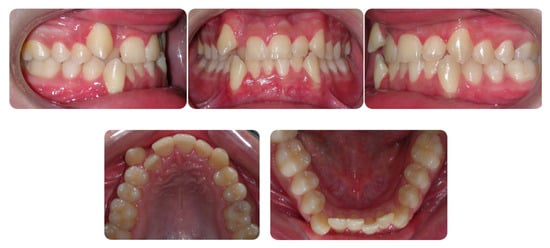

2.1. Diagnosis and Etiology

2.5. Results